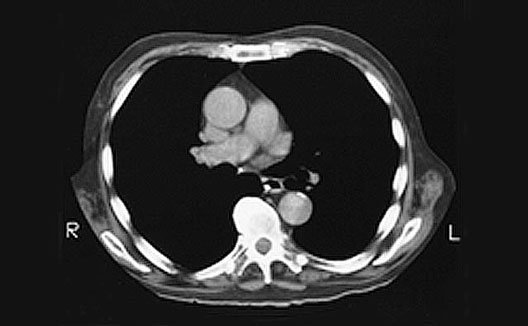

Heart CT

1. Ascending aorta

2. Right pulmonary artery

3. Pulmonary trunk

4. Descending aorta